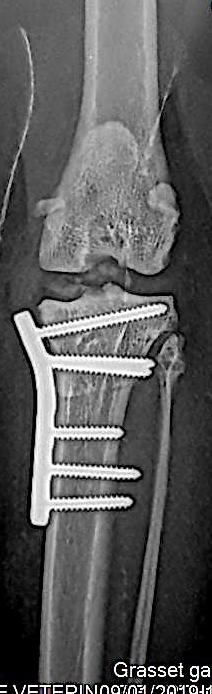

Cas clinique : Abaissement du Plateau Tibial (TPLO) chez le chat

Découvrez un cas clinique d’abaissement du plateau tibial chez le chat. Cette procédure de TPLO a été réalisé par la clinique vétérinaire Orthovet à Montpellier.

radio TPLO chat

La miniaturisation des implants permet aujourd’hui de proposer cette technique chez le chat avec succès.

Le résultat fonctionnel est remarquable avec 95% de très bonnes récupérations fonctionnelles annoncées.